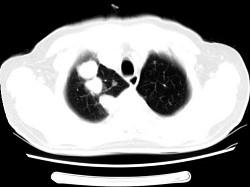

问题 男,64岁,咳嗽半月,咯血一天,不发热,结合影像图像选择最可能的诊断 ( )

选项 A、结节病 B、组织胞浆菌病 C、肺转移性瘤 D、肺结核 E、金葡菌肺炎

答案 C